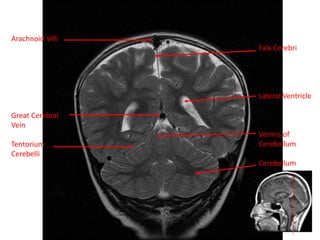

Arachnoid Villi

Great Cerebral

Vein

Tentorium

Cerebelli

Falx Cerebri

Lateral Ventricle

Vermis of

Cerebellum

Arachnoid Villi Great Cerebral Vein Tentorium Cerebelli FalxCerebri Lateral Ventricle Vermis of Cerebellum Cerebellum

• 62.